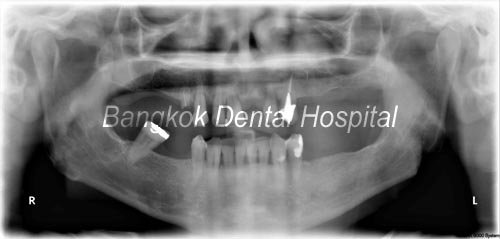

prima

prima all-on-4 x-ray